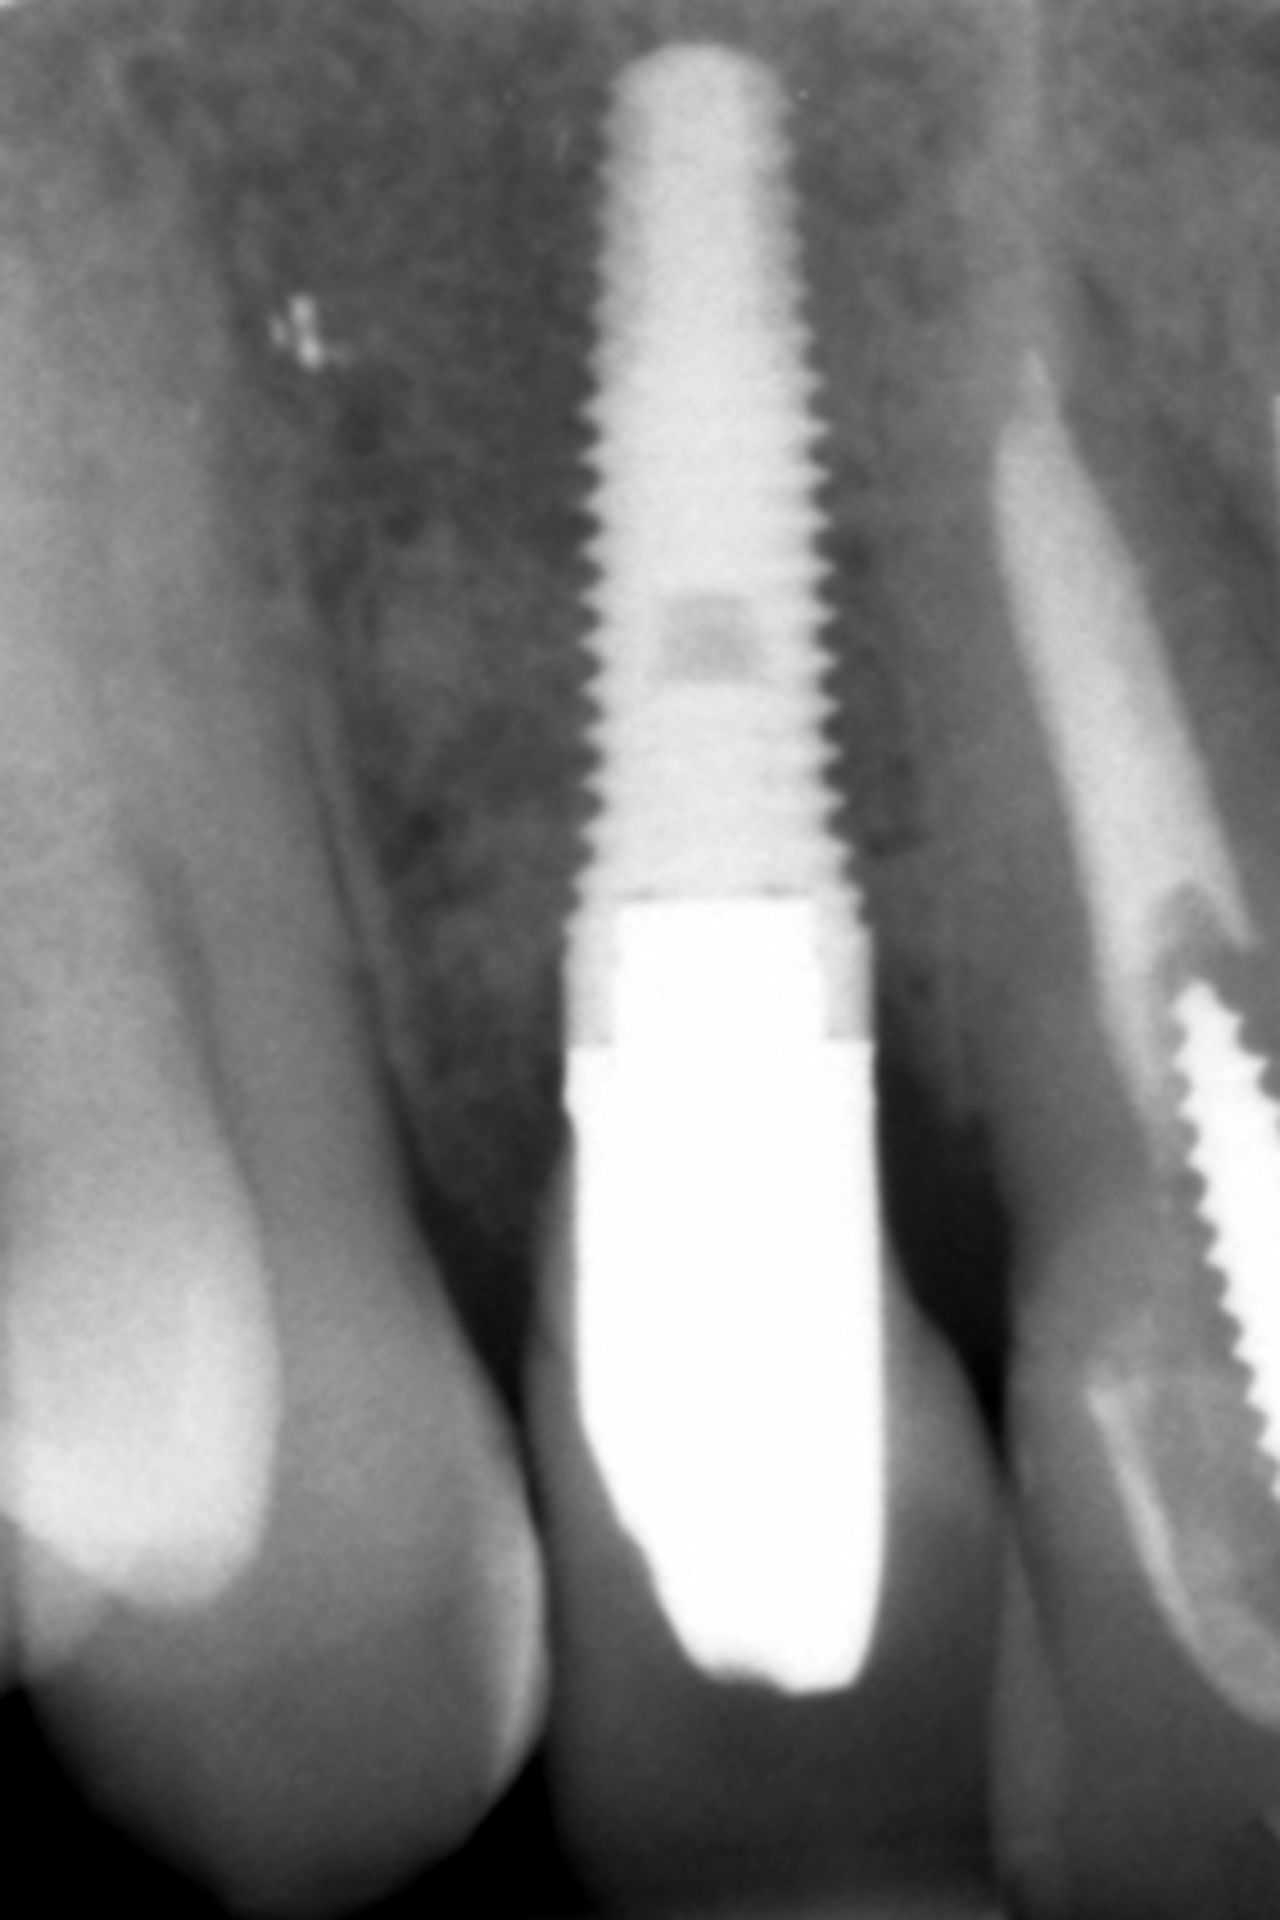

Métodos: Se llevó a cabo un caso clínico en una paciente de 40 años con fracaso de restauración fija dentosoportada en el incisivo central superior izquierdo, asociado a caries radicular subgingival con mal pronóstico restaurador. Tras la evaluación clínica y radiográfica, se indicó la exodoncia atraumática del diente afectado. Inmediatamente después, se realizó la colocación de un implante postextracción. El defecto periimplantario (gap) fue rellenado con un xenoinjerto óseo bovino. De forma simultánea, se llevó a cabo un injerto de tejido conectivo con el objetivo de optimizar el volumen y la estabilidad de los tejidos blandos periimplantarios. Se procedió a la colocación de una restauración provisional inmediata atornillada, diseñada para preservar el perfil de emergencia y guiar la cicatrización de los tejidos periimplantarios. Tras un periodo de cicatrización de cuatro meses, se colocó la restauración definitiva atornillada.

Resultados: El seguimiento clínico y radiológico evidenció una correcta osteointegración, estabilidad de los tejidos periimplantarios y un resultado estético satisfactorio, mantenido a los cuatro años.